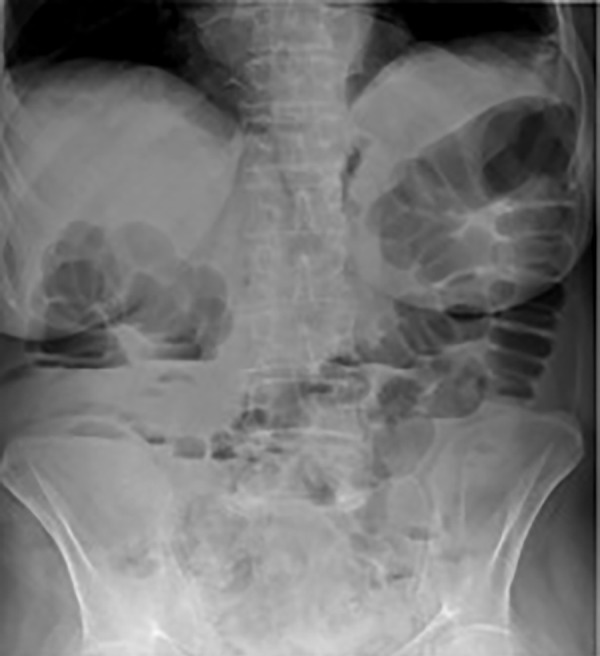

Two years later, there was a new clinical worsening, including diarrhoea, of the same clinical features, occurring predominantly at night, and severe dehydration. No metabolic–electrolyte abnormalities were found, except for elevated serum urea nitrogen (130 mg/dL) and serum creatinine (1.54 mg/dL). The patient was admitted to the internal medicine ward for further aetiological research and acute renal failure treatment. New blood and stool tests (table 1 and 2) were performed and, once more, revealed no changes. The abdomen X-ray and CT scan showed marked colonic and small bowel distension (figures 1 and 2). Sigmoidoscopy demonstrated pseudomembranous colitis (figure 3), and endoscopy and videoenteroscopy presented no abnormalities. The patient was started on therapy with metronidazole and vancomycin (14 days), with parenteral nutrition, which resulted in no improvement. Later, a gluten-free and lactose-free diet was introduced, but with an ileus and diarrhoea maintenance. On the 14th day of hospitalisation, for a suspected iatrogenic cause, all AD were suspended, with a complete resolution of diarrhoea and AI. The colonoscopy performed at discharge was normal.

Figure 1.

An exuberant adynamic ileus in abdomen X-ray.